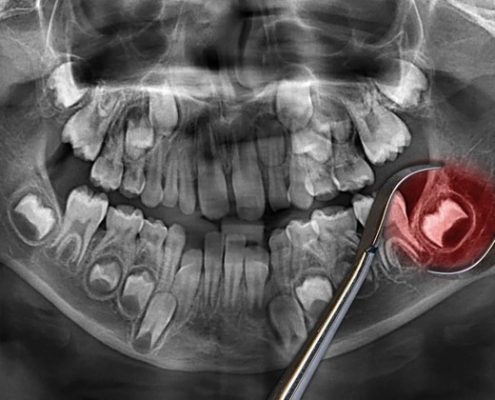

علت ترک دندان و درمان آن

ترک دندان گاهی منجر به شکستن و از بین رفتن دندان می شود. کمبود کلسیم یکی از عوامل ترک دندان محسوب می شود انواع ترک های دندان: شکستگی کاسپ، ترک ریشه دندان و.